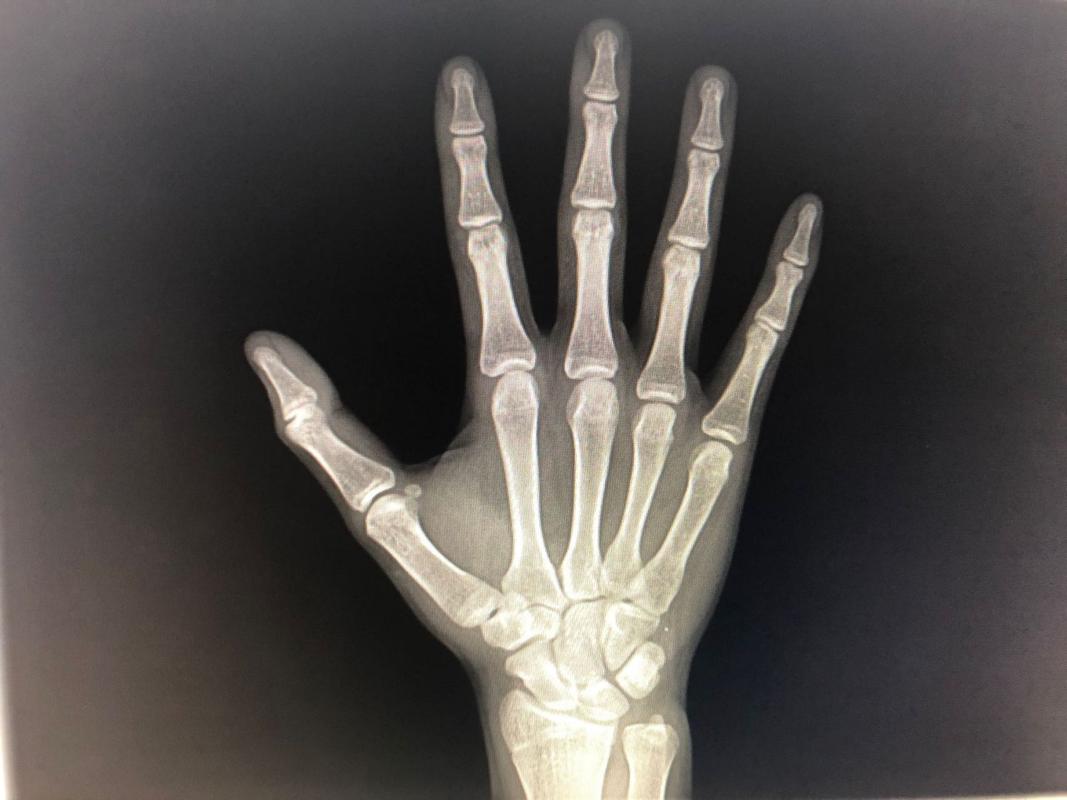

目前越来越多的家长注意孩子的骨龄,经常带着孩子到医院进行相应的检测,在骨龄检测的时候通过手腕测量是最准确的, 在检测出孩子的骨龄之后,接下来还需要配合孩子的生长速度以及生长曲线等因素来作出判断 。